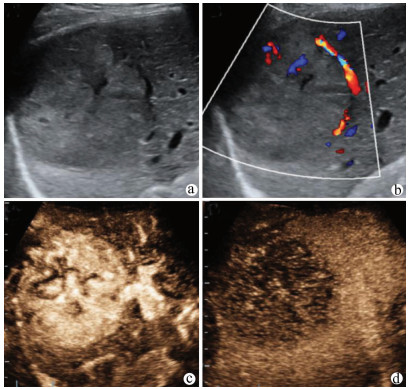

肝病超声诊断指南

中华医学会超声医学分会, 中国研究型医院学会肿瘤介入专业委员会, 国家卫生和健康委员会能力建设和继续教育中心超声医学专家委员会

2021, 37(8): 1770-1785. DOI: 10.3969/j.issn.1001-5256.2021.08.007

摘要(3138) HTML (6640) PDF (9311KB)(810)

摘要:

超声检查无创、实时、价廉,无辐射、便于反复进行,是最常用的肝脏影像学检查方法。近年来,超声检查新技术如超声造影、弹性成像发展迅速,可有效鉴别肝内占位性病变性质、评估肝纤维化和门静脉高压程度以及监测肝病治疗效果,在临床肝病及其介入治疗中发挥重要诊断价值。本指南规范了肝病多模态超声技术(灰阶超声、彩色多普勒超声、超声造影、弹性超声)检查的仪器调置、患者准备及医生检查方法;对肝脏弥漫性病变(炎性病变、纤维化、硬化)、多种占位性病变及肝病介入操作的多模态超声技术诊断标准进行了定义和规范,同时推荐了超声监测周期及肝脏疾病超声诊断报告书写规范。